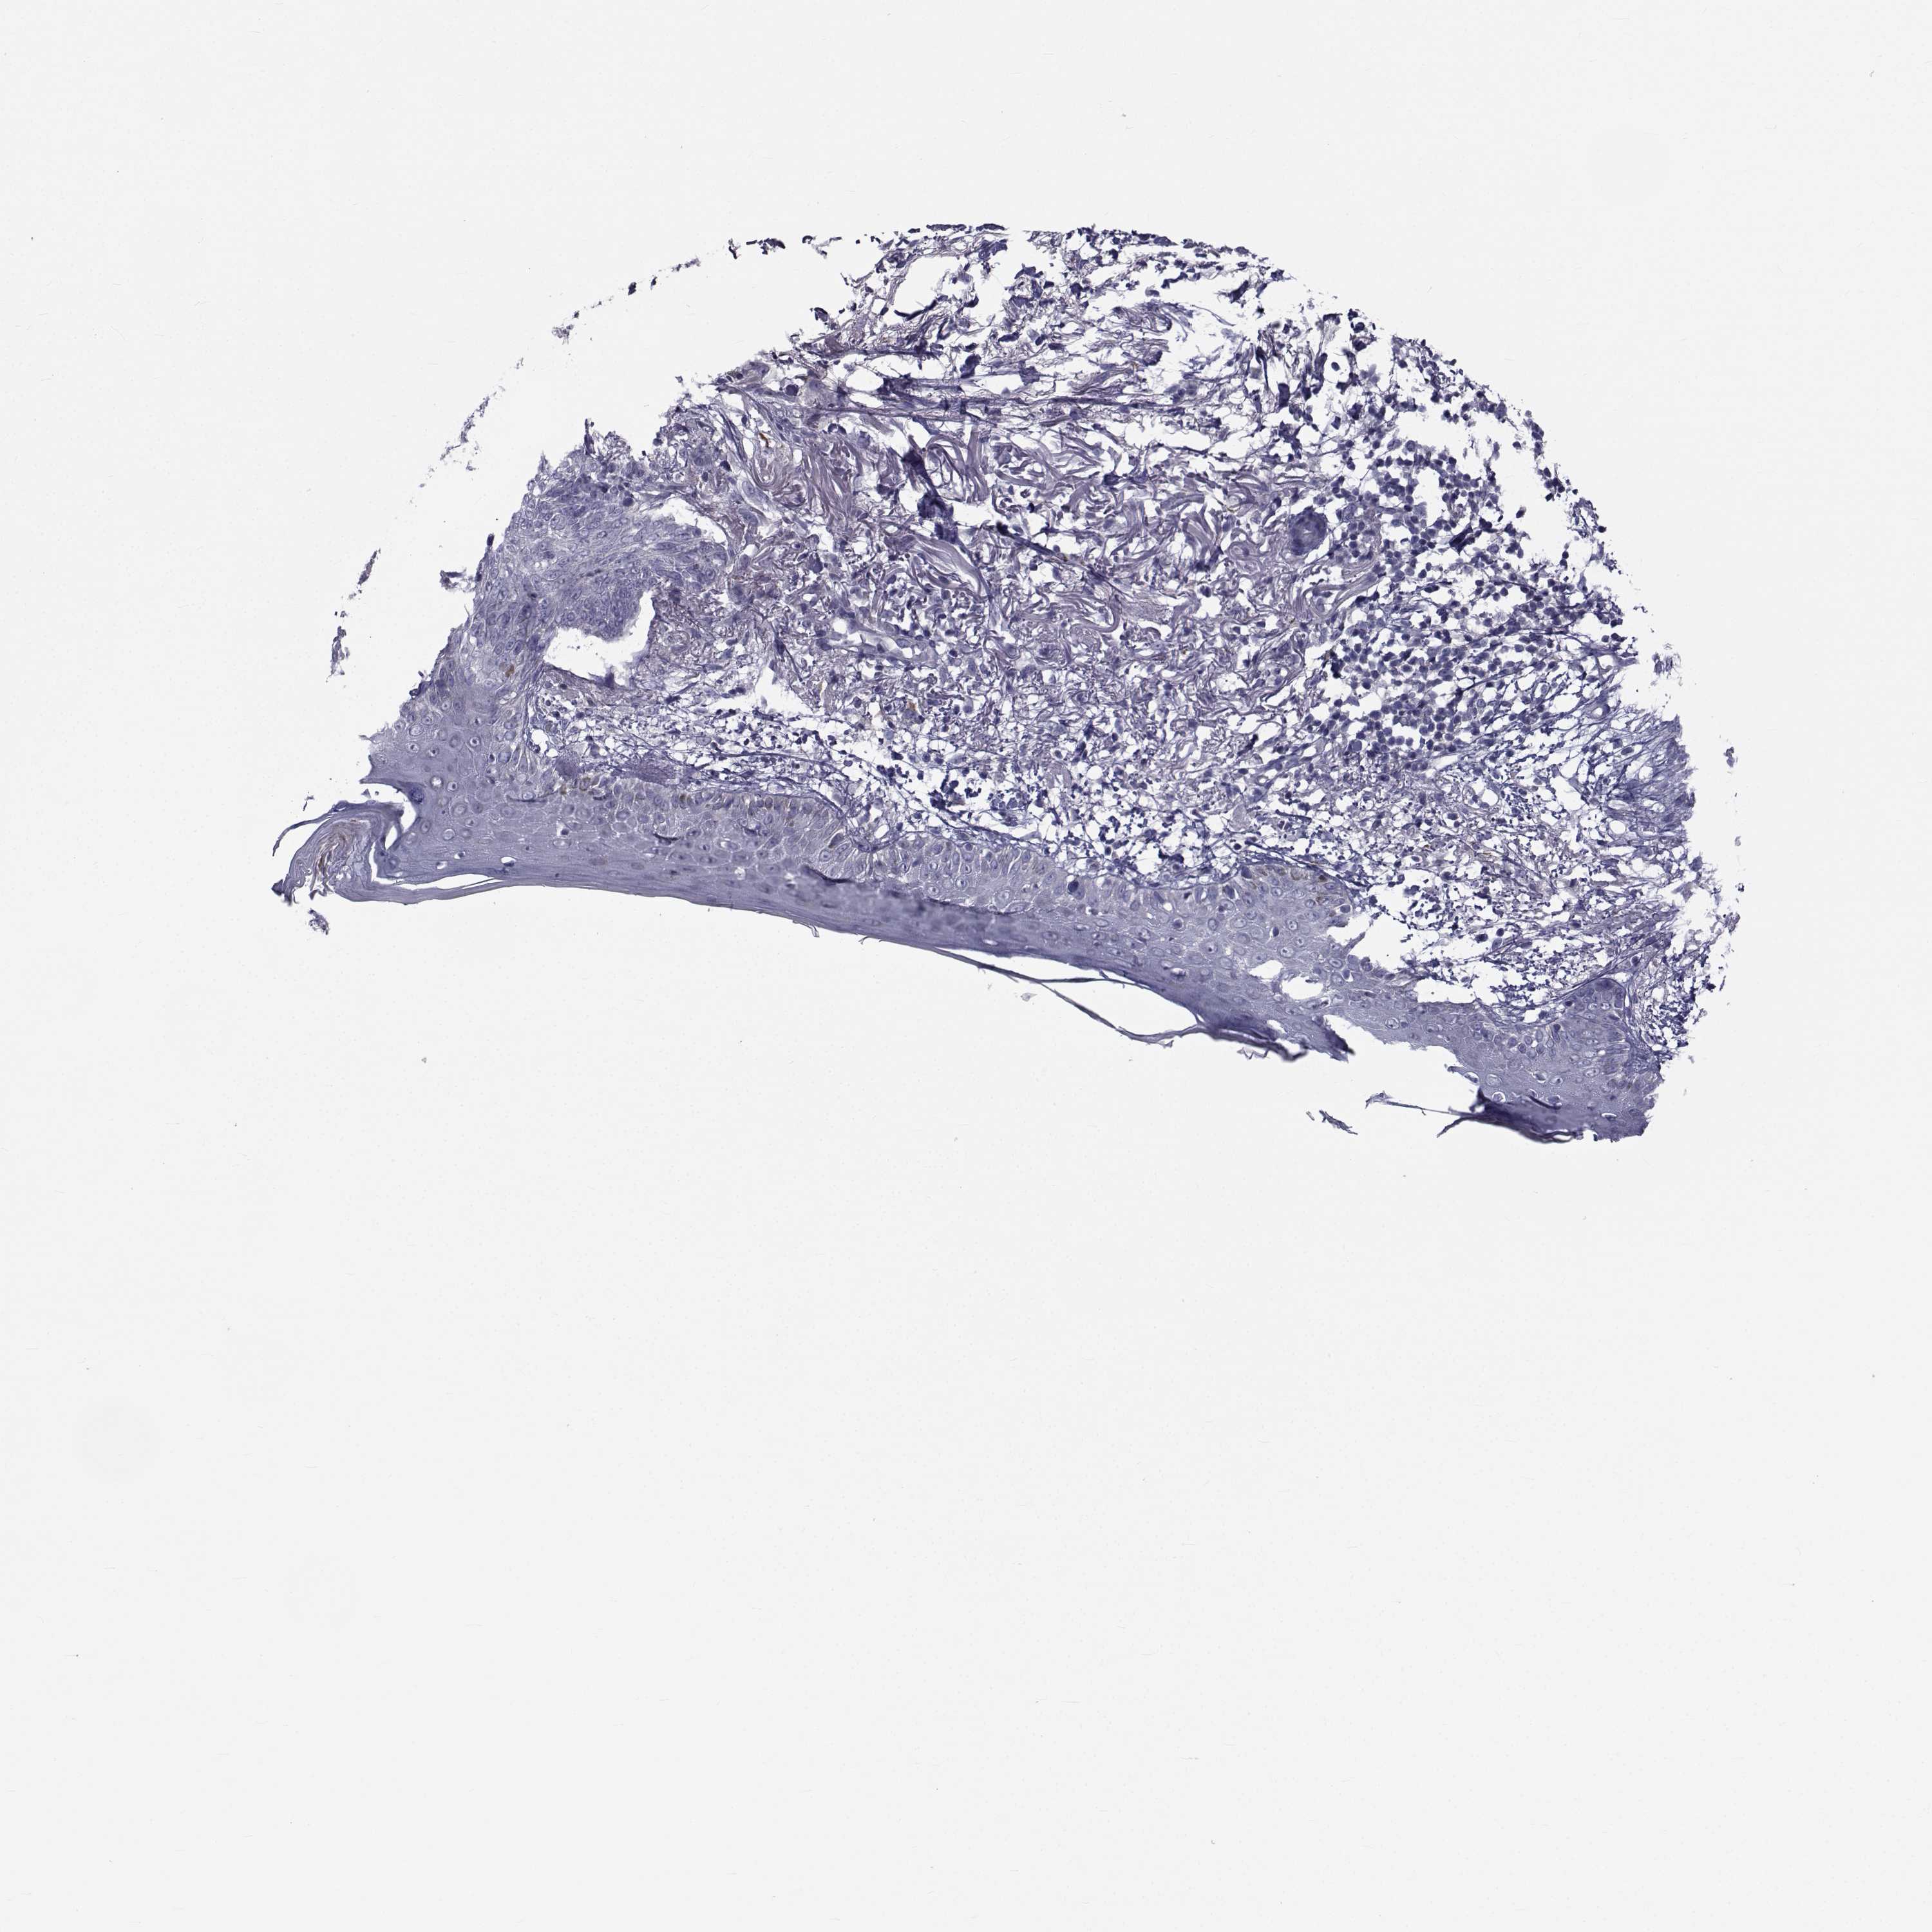

SKIN CANCER - Protein expressioni

A mouse-over function shows sample information and annotation data. Click on an image to view it in a full screen mode. Samples can be filtered based on level of antibody staining by selecting one or several of the following categories: high, medium, low and not detected. The assay and annotation is described here.

Each image is clickable and will lead to virtual microscopy that enables deeper exploration of all samples and also displays staining intensity scores, fraction scores and subcellular localization as well as patient and tissue information for each sample.

Antibody HPA044393

Antibody HPA053673

Antibody CAB009818

Staining

High

Medium

Low

Not detected

Intensity

Strong

Moderate

Weak

Negative

Quantity

>75%

75%-25%

<25%

None

Location

Nuclear

Cytoplasmic/membranous

Cytoplasmic/membranous,nuclear

Squamous cell carcinoma, NOS

Basal cell carcinoma